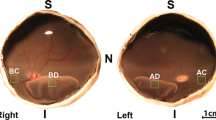

BNN27 does not induce TrkA phosphorylation, although the mRNA levels of the receptor are elevated in the detached photoreceptors

NGF has been extensively studied in retinal degenerations4,36,37,38,39,40,41,42,43, however, the expression of its receptors, TrkA and p75NTR in healthy19,38,39,44,45,46,47,48 and degenerated38,42,44,45,46,48 photoreceptors has not been fully elucidated. To clarify this point, we examined the mRNA levels of TrkA and p75NTR in the outer nuclear layer (ONL) in both healthy and detached retina by laser capture microdissection (LCM) (Fig. 4A). TrkA mRNA was not detected in the ONL before injury while it was robustly increased 24 hours post RD (Fig. 4B, n = 4–5). On the contrary, there was no significant change in the mRNA levels of p75NTR before and after injury (Fig. 4B, n = 4–5), indicating that at least in the photoreceptors p75NTR does not play an instrumental role following RD. BNN27 selectively binds to TrkA receptor leading to its phosphorylation and promoting neuroprotection in a TrkA-dependent manner27. We have previously shown that phosphorylation, thus activation of TrkA, is elevated following experimental RD4. To assess if BNN27 can further upregulate TrkA activation, we examined the phosphorylation of the receptor on Y490 residue and the downstream signaling which leads to neuronal survival and differentiation in BNN27-treated and untreated detached retinas. Interestingly, phosphorylation of TrkA was not significantly increased in the BNN27-treated group and consequently neither was phosphorylation of Akt or Erk (phosphorylated-to-total ratio, Fig. 4C, n = 4).

Expression of TrkA and p75NTR in photoreceptors and effect of BNN27 on TrkA phosphorylation and downstream signaling following RD. (A) Representative pictures of retinal sections before and after cutting the ONL with LCM from attached and detached retina. Nuclei were stained with toluidine blue. (B) TrkA and p75NTR mRNA expression in the ONL following isolation of the photoreceptors’ nuclei with LCM. TrkA mRNA levels were not detected in the attached retina while they were significantly elevated in the detached, n = 4–5. On the contrary, p75NTR mRNA levels were not altered before and after injury, n = 4–5. (C) Western blotting images and densitometry analysis of phosphorylated TrkA, total TrkA, phosphorylated Erk, total Erk, phosphorylated Akt and total Akt of detached retinas between untreated and BNN27-treated eyes. BNN27 did not further induce phosphorylation of TrkA, Erk or Akt, n = 4. Scale bar: 100 μm. The graphs show mean ± SEM. RD, Retinal Detachment, ONL, Outer Nuclear Layer, LCM, Laser Capture Microdissection, ND, Not Detectable.